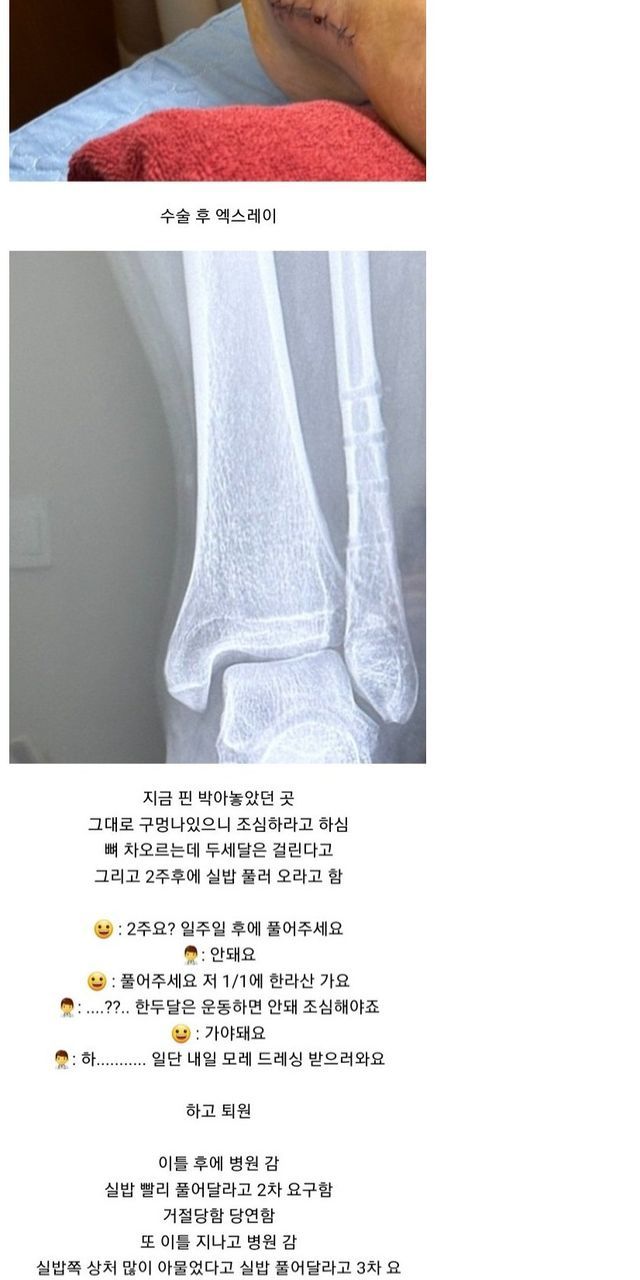

빙판길에서 자빠져 발목 부러져서 수술

수술했는데 하나도 안아픔

한달 뒤 멀쩡하게 걸어다녀서 나중에 의사가 보고 화들짝